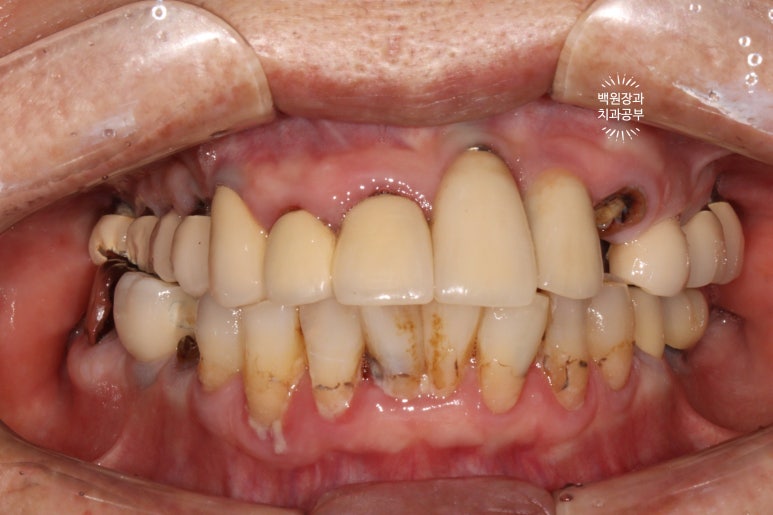

처음 오셨을 때 정면 사진입니다.

잘 보시면, 아까 보였던 치과용 파노라마 사진대로 뿌리만 남은 두 개의 치아를 찾아보실 수 있으실거에요. ㅎㅎ

제가 서두에서 어금니에 스트라우만 임플란트가 많다고 말씀드렸는데, (나머지도 branemark 제품으로 보이며, 명품으로 주름잡던 스웨덴 임플란트 입니다.) 이 미친 퍼포먼스의 스위스 임플란트는 20년이 지난 지금도 짱짱한 성능을 자랑하고 있답니다.

사실 구강위생관리가 그렇게 완벽하신편이 아니신데도.. 이런 임상결과를 보이고 있는 것이 늘 경이롭습니다.